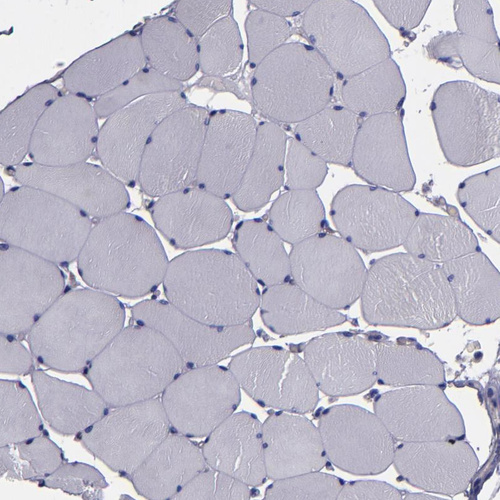

Immunohistochemistry analysis in human cerebral cortex and skeletal muscle tissues using Anti-CARS antibody. Corresponding CARS RNA-seq data are presented for the same tissues.